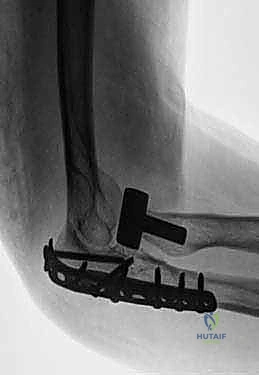

TECH FIG 2 • ( continued ) C. Postoperative radiograph of a Monteggia fracture in which the radial head fracture needed to be replaced.

* Definitive Fixation: Apply a rigid plate to the dorsal cortex of the ulna, extending proximally over the olecranon. This plate will typically be a pre-contoured olecranon plate or a specifically designed Monteggia plate.

TECH FIG 3 • ( continued ) D. Final fixation for most Monteggia fractures is with a rigid plate applied to the dorsal cortex.